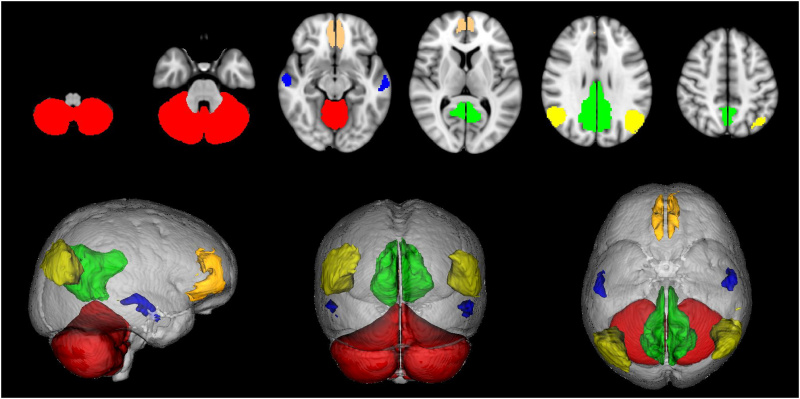

In effetti la solitudine di cui ci parla Pennisi non è né uno stato eccezionale né, tantomeno, uno stato patologico, una condizione da evitare e, se possibile, da ‘curare’. L’ottava solitudine, al contrario, quella specificamente umana (le altre le condividiamo più o meno con tutti gli altri viventi), coincide con la condizione normale, quasi fisiologica, del cervello umano. È quella che i neuroscienziati indicano come Default Mode Network (DMN) del cervello umano, ossia la condizione del cervello quando non è impegnato in qualche altra attività, quando cioè non è impegnato nel compiere una azione o nel pensare a qualcosa. Quando il cervello non ha niente da fare allora quel cervello, per così dire, si concentra su sé stesso, si pensa. La scoperta di questa condizione di base deriva dall’idea di “alcuni ricercatori” di “testare il cervello quando non sta facendo nulla. Dal punto di vista sperimentale, si monitora con la fMRI” – cioè la risonanza magnetica funzionale, o appunto fMRI, che è una particolare risonanza magnetica che viene utilizzata per individuare quali aree cerebrali si attivano durante l’esecuzione di un certo compito (ad esempio parlare, leggere, muovere una mano e così via) – “il cervello di un individuo che viene lasciato rannicchiato e solo all’interno del cilindro blindato in cui avviene la risonanza magnetica con, al massimo, un piccolo punto luminoso da fissare. È questo il caso non metaforico della solitudine cerebrale, chiamata tecnicamente attività intrinseca” (p. 128).